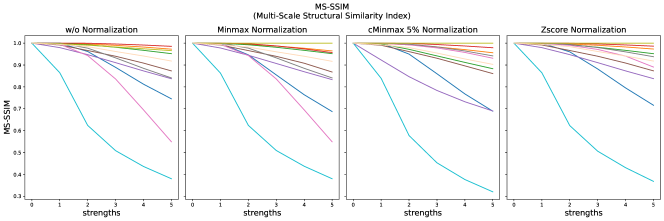

The results for all strengths are given in Figs. A.1-A.4. In Tab. 5 - 8, the results for distortions of maximal strength (s=5) are summarized.

For all applied distortions, all reference metric scores monotonously measure lower similarity for increasing distortion strengths.

SSIM similarity scores for strong blurring are very high, compared to most other distortions.

PSNR scores generally display only very small changes for strengths larger than 2 (see Fig. A.1). PSNR values are higher for Zscore normalization.

Images distorted with Gaussian blurring and ghosting artifacts receive very high PSNR similarity scores, especially with small distortion strengths.

The experiments and adverse examples demonstrate specific strengths and weaknesses of the analyzed metrics. Although SSIM and PSNR are frequently used for the evaluation of synthetic MR images, they are strongly decreased by constant intensity shifts if no normalization is applied. PSNR is very dependent on the kind of normalization, which complicates its use as a comprehensive metric for comparing studies of different authors. SSIM underestimates blurring and thereby favors blurred or additionally blurred images over other distortions.